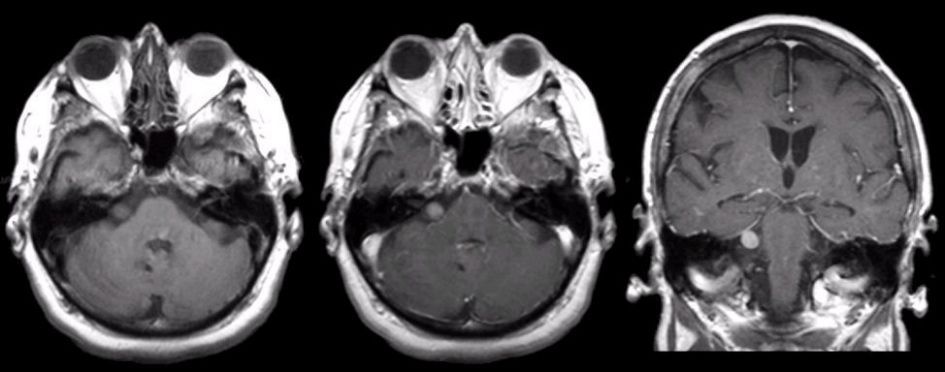

Acoustic neuroma is a benign tumor. It is also known as vestibular schwannoma. The symptoms of acoustic neuroma include dizziness, hearing impairment, tinnitus, and unsteadiness. Reference: https://www.mayoclinic.org/diseases-conditions/acoustic-neuroma/symptoms-causes/syc-20356127 Image via: https://www.mayoclinic.org/diseases-conditions/acoustic-neuroma/symptoms-causes/syc-20356127